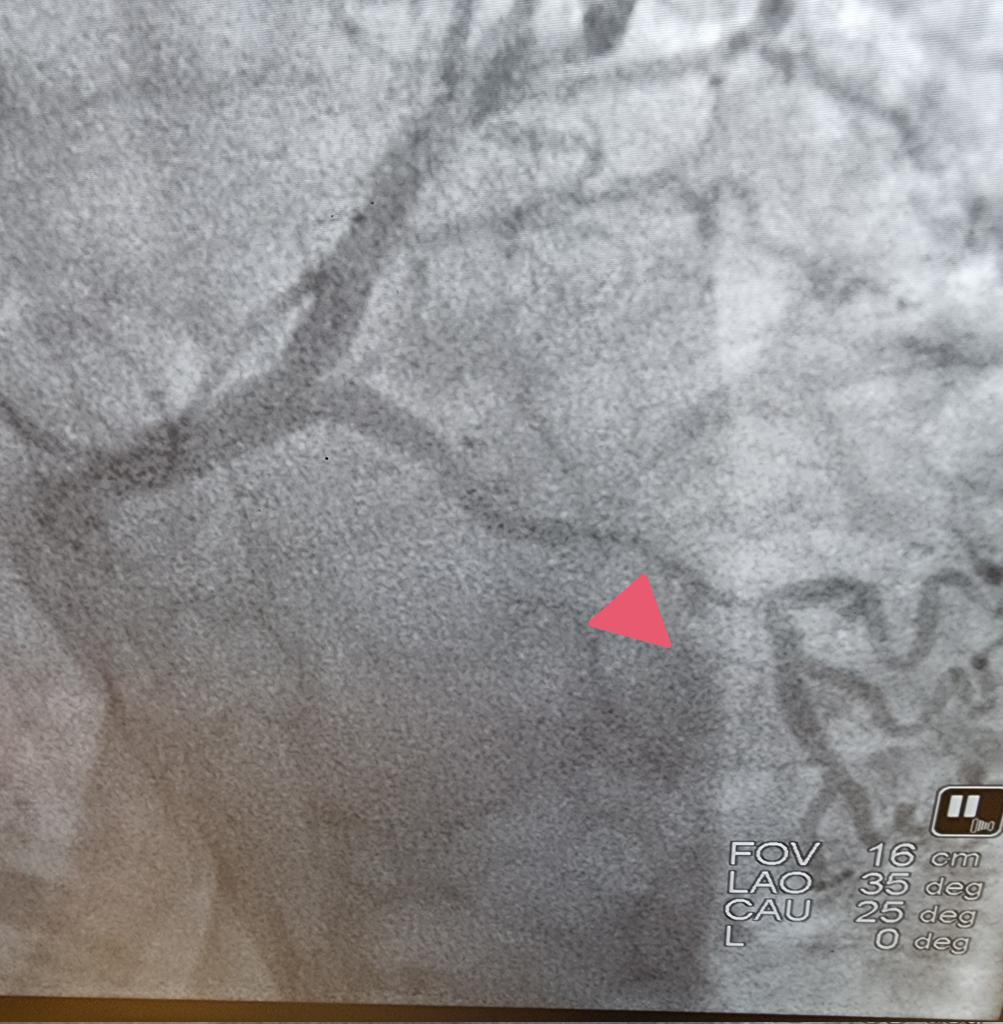

للتو خرجت من قسطرة كانت لمريض سكري وضغط وارتفاع كلسترول يشتكي ألماً شديداً في الصدر....فظهر تضيق شديد في أحد الشرايين التاجية وتمت معالجته. والحمد لله

أ.د.خالد النمر tweet mediaأ.د.خالد النمر tweet media